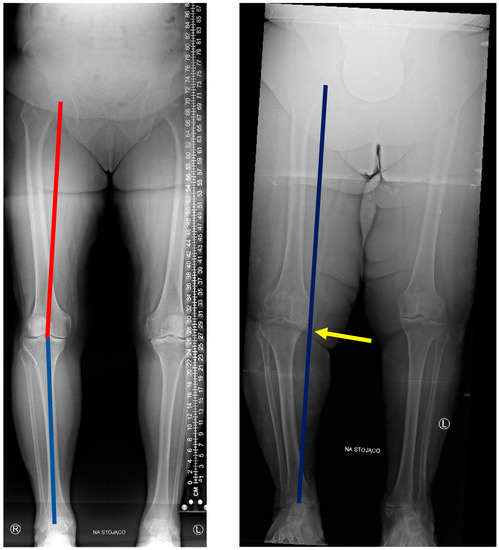

2.2.2. X-ray Measurement of the Lower Limb Axis

In the second stage of the radiological assessment, the mechanical axis of the operated lower limb was plotted. The measurement was carried out using radiological pictures on a long measuring film in a digital form. The measurement was conducted in a standing position, with a full load on the limbs. The radiological examination covered the anatomical area from the iliac plates to the feet, with the necessary consideration of the heads of the femurs and blocks of the talus on both sides, as shown in Figure 4.

The measurements were carried out using the method of plotting the mechanical axis of the lower limb, using the HKA angle, with the classification of varus deformity used in The Journal of Arthroplasty [20], in which the HKA angle equal to and lower than 177° is considered to be a varus deformity of the joint, divided into stages. For the sake of clarity, the degree of deformation is defined as the angle complementary to the angle of 180°. Below 3°, the result was normal; a value in the range of 4°–10° is considered a slight deformation. In the range of 11°–20°, the deformation is defined as notable. Significant deformation occurs in the range of 21°–30°, while beyond 30°, the deformation is defined as extreme.

The exact measurement of the axis of the lower limb was determined in accordance with the previously presented classification. The measurement was conducted by marking a line running from the center of the femoral head to the knee joint and from the center of the knee joint to the center of the talus block, followed by measuring the angle between the marked lines and assigning it to the appropriate angle HKA, described above (Figure 4).

Figure 4. Measurement X-ray of the lower limbs in a patient with a slight varus deformity of the knee joint (left) and an advanced deformity (right). On the left, HKA angle is presented: red line shows hip–knee line; blue line shows knee–ankle line. On the right: narrowing of the medial compartment (yellow arrow) affecting the mechanical axis of the limb (blue line). The line moved medially indicates varus deformity of the knee joint. Source: proprietary material (description “na stojąco” [pl] means in the weightbearing position).